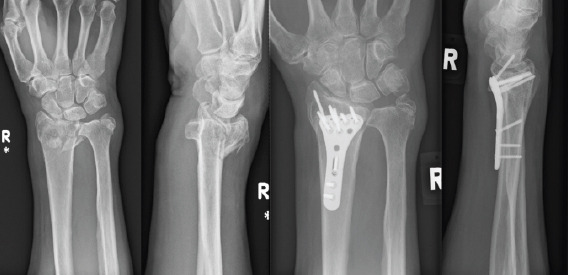

Materials & methods: This retrospective study analyses medical records of patients diagnosed with acute carpal tunnel syndrome from 2021 to 2023 within our coverage area. Information was extracted from medical records, including diagnostic codes and clinical assessments for all cases of acute carpal tunnel syndrome, diagnosed during the period from 2021 to 2023. Data analysed, include age, sex, medical history, symptoms, mechanism of injury, clinical features, imaging, management, and follow-up. Six native Scottish patients, aged 43 to 65, developed acute carpal tunnel syndrome due to various causes, including flexor sheath infection, wrist soft tissue injury, distal radius fractures (with and without plate fixation), and scaphoid fracture.